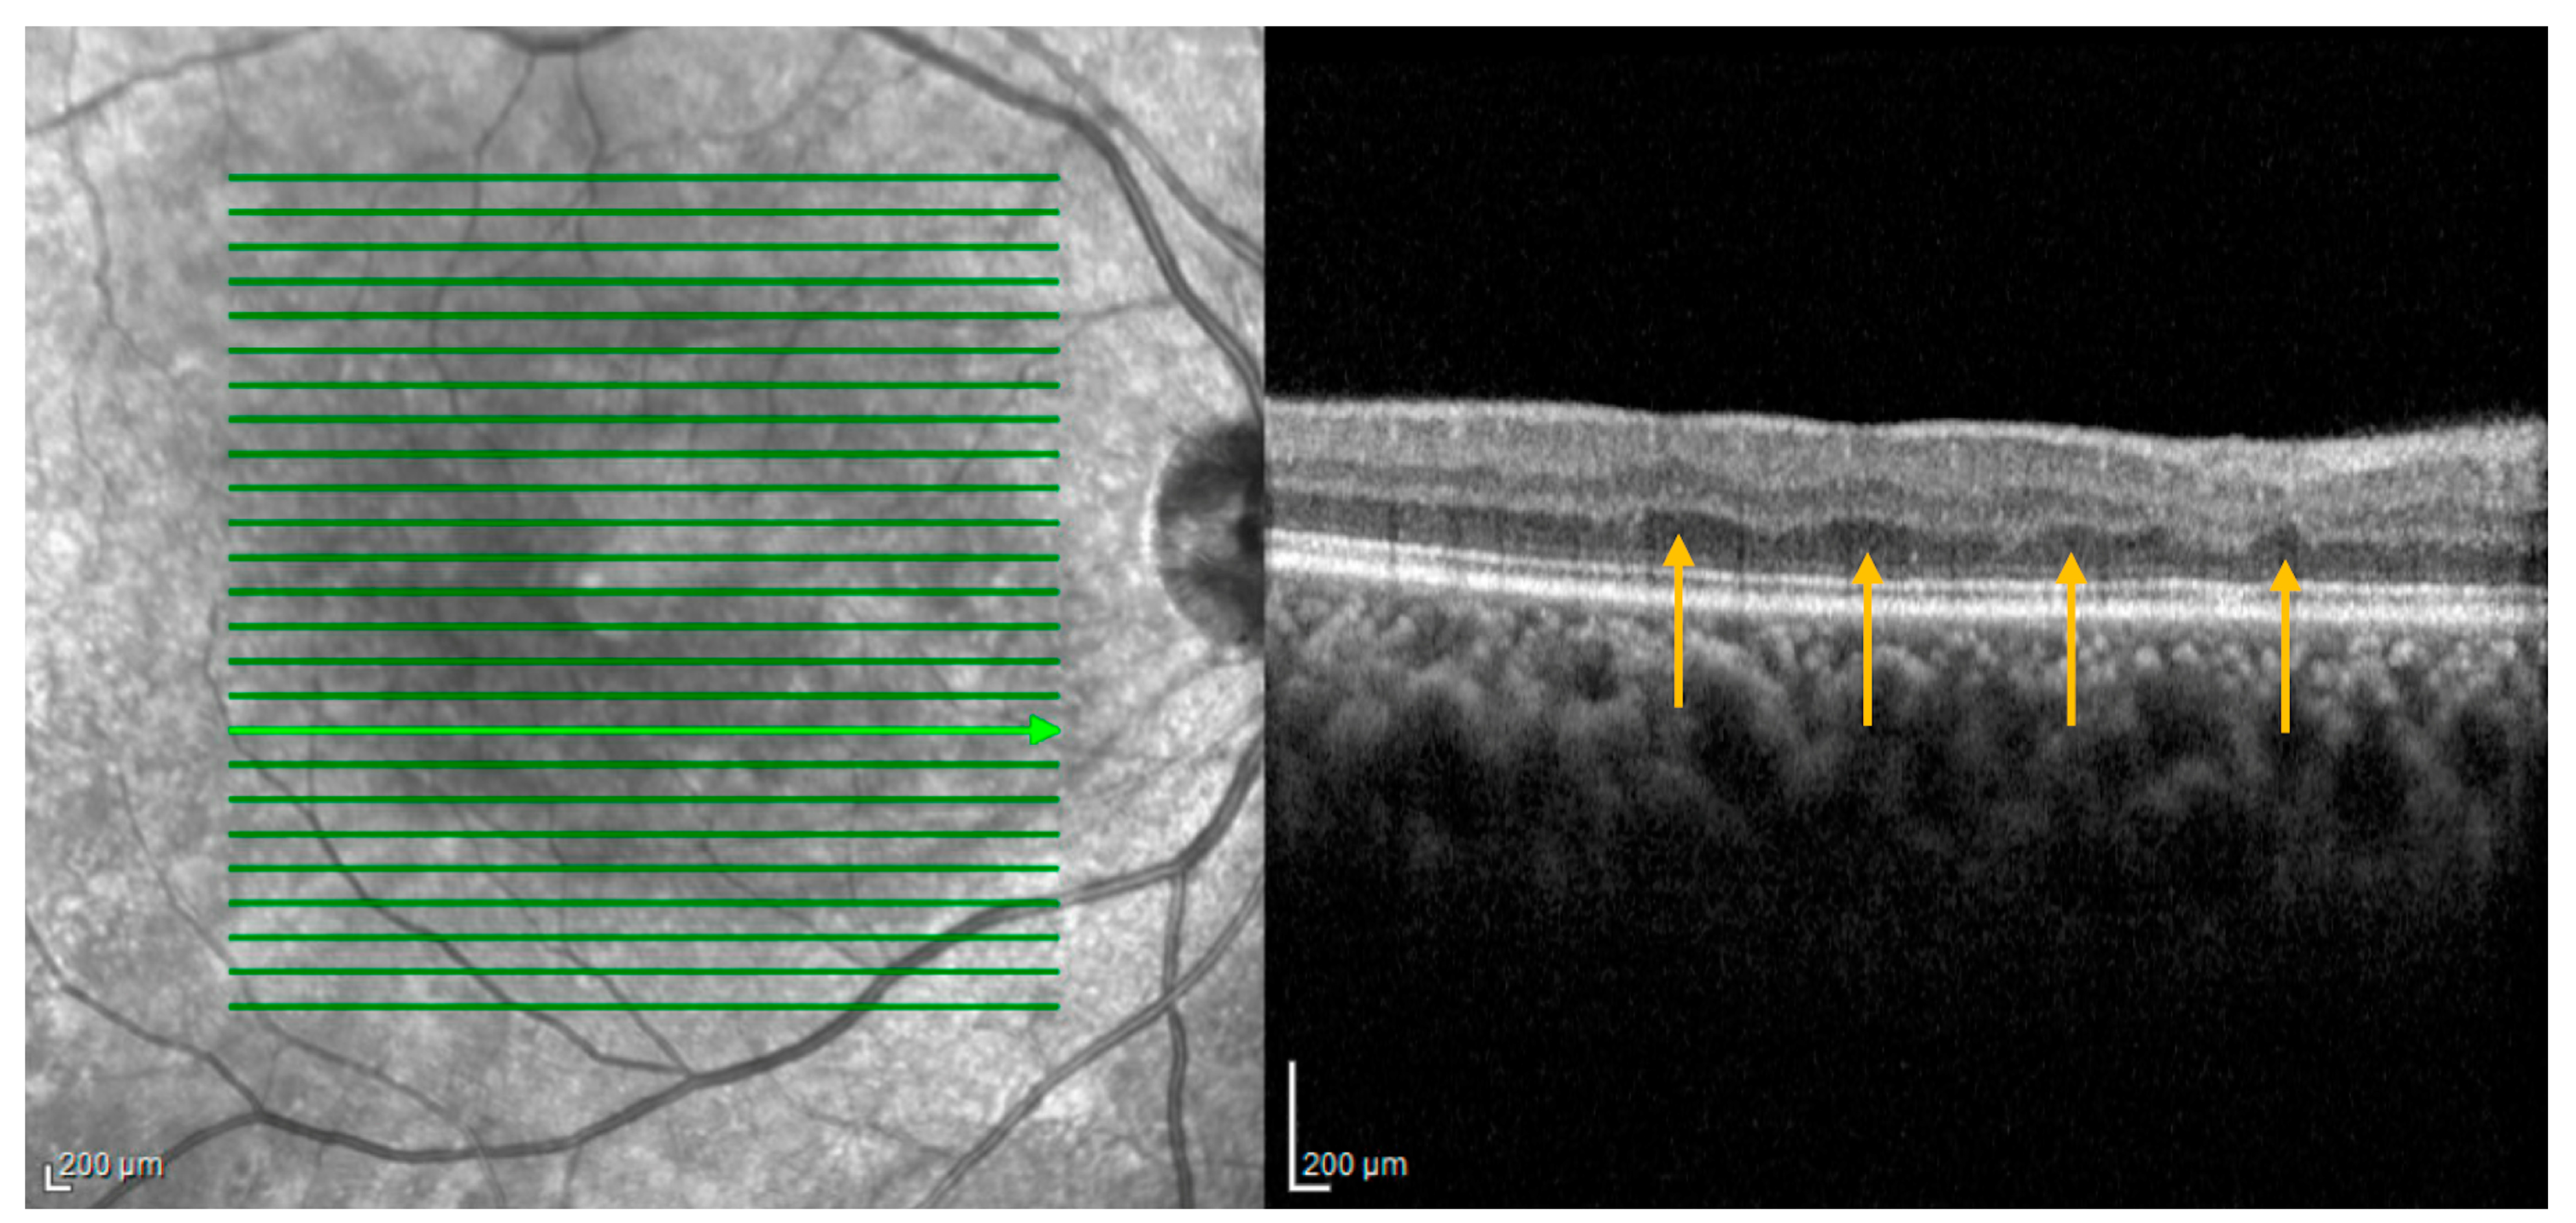

3.3.2. Retinal Ischemic Perivascular Lesions (RIPLs)

Optical coherence tomography findings known as retinal ischemic perivascular lesions (RIPLs) were recently described in the literature []. RIPLs are characterized by focal atrophy of the inner nuclear layer (INL) accompanied by secondary expansion of the outer nuclear layer, resulting in an undulating appearance of the middle retinal layers (Figure 5). RIPLs are thought to arise at the sites of previous middle retinal layer infarcts, potentially evolving as a subsequent manifestation of paracentral middle maculopathy (PAMM), wherein the hyperreflective inner nuclear band observed during the acute phase gradually undergoes atrophy over time. PAMM has not been conclusively shown to confer increased cardiovascular risk. However, RIPLs do appear to be representative of end-organ infarction secondary to vascular dysfunction and are linked with cardiovascular disease.

A retrospective study of 160 subjects demonstrated a higher number of RIPLs in individuals with cardiovascular disease and, crucially, found that each additional RIPL identified on imaging conferred greater odds of cardiovascular disease, after adjusting for age, sex, and smoking status []. The presence of 1, 2, or 3 RIPLs was associated with an increased odds ratio of developing CVD of 2.3, 4.2, and 5.3, respectively, after adjusting for multiple covariables. Moreover, patients with intermediate or high 10-year ASCVD (atherosclerotic cardiovascular disease) risk scores were found to have more RIPLs than patients with low or borderline ASCVD risk scores. RIPLs have also been explored as an occult imaging biomarker for systemic cardiovascular disease. In a recent study, 8 of 11 (72.7%) patients with RIPLs and no prior diagnosis of cardiovascular disease were found to have newly diagnosed CVD upon further workup with their primary care physician or cardiologist []. Two of these patients required surgical intervention, including coronary artery bypass graft and carotid artery stent placement, and 3 were started on new medications. Despite the report’s limited sample size, the profound implications of the findings underscore the importance of considering cardiovascular evaluation in patients with RIPLs. These lesions, reasonably considered a new ophthalmic imaging biomarker of cardiovascular disease, may encourage ophthalmologists to refer their patients for age-appropriate cardiovascular disease screening (at minimum, serial blood pressure monitoring, lipid profile, and hemoglobin A1C). Patients in the aforementioned study also underwent electrocardiography and echocardiogram, with carotid duplex and ambulatory ECG also revealing abnormalities, in some cases resulting in invasive cardiac testing or surgical intervention.